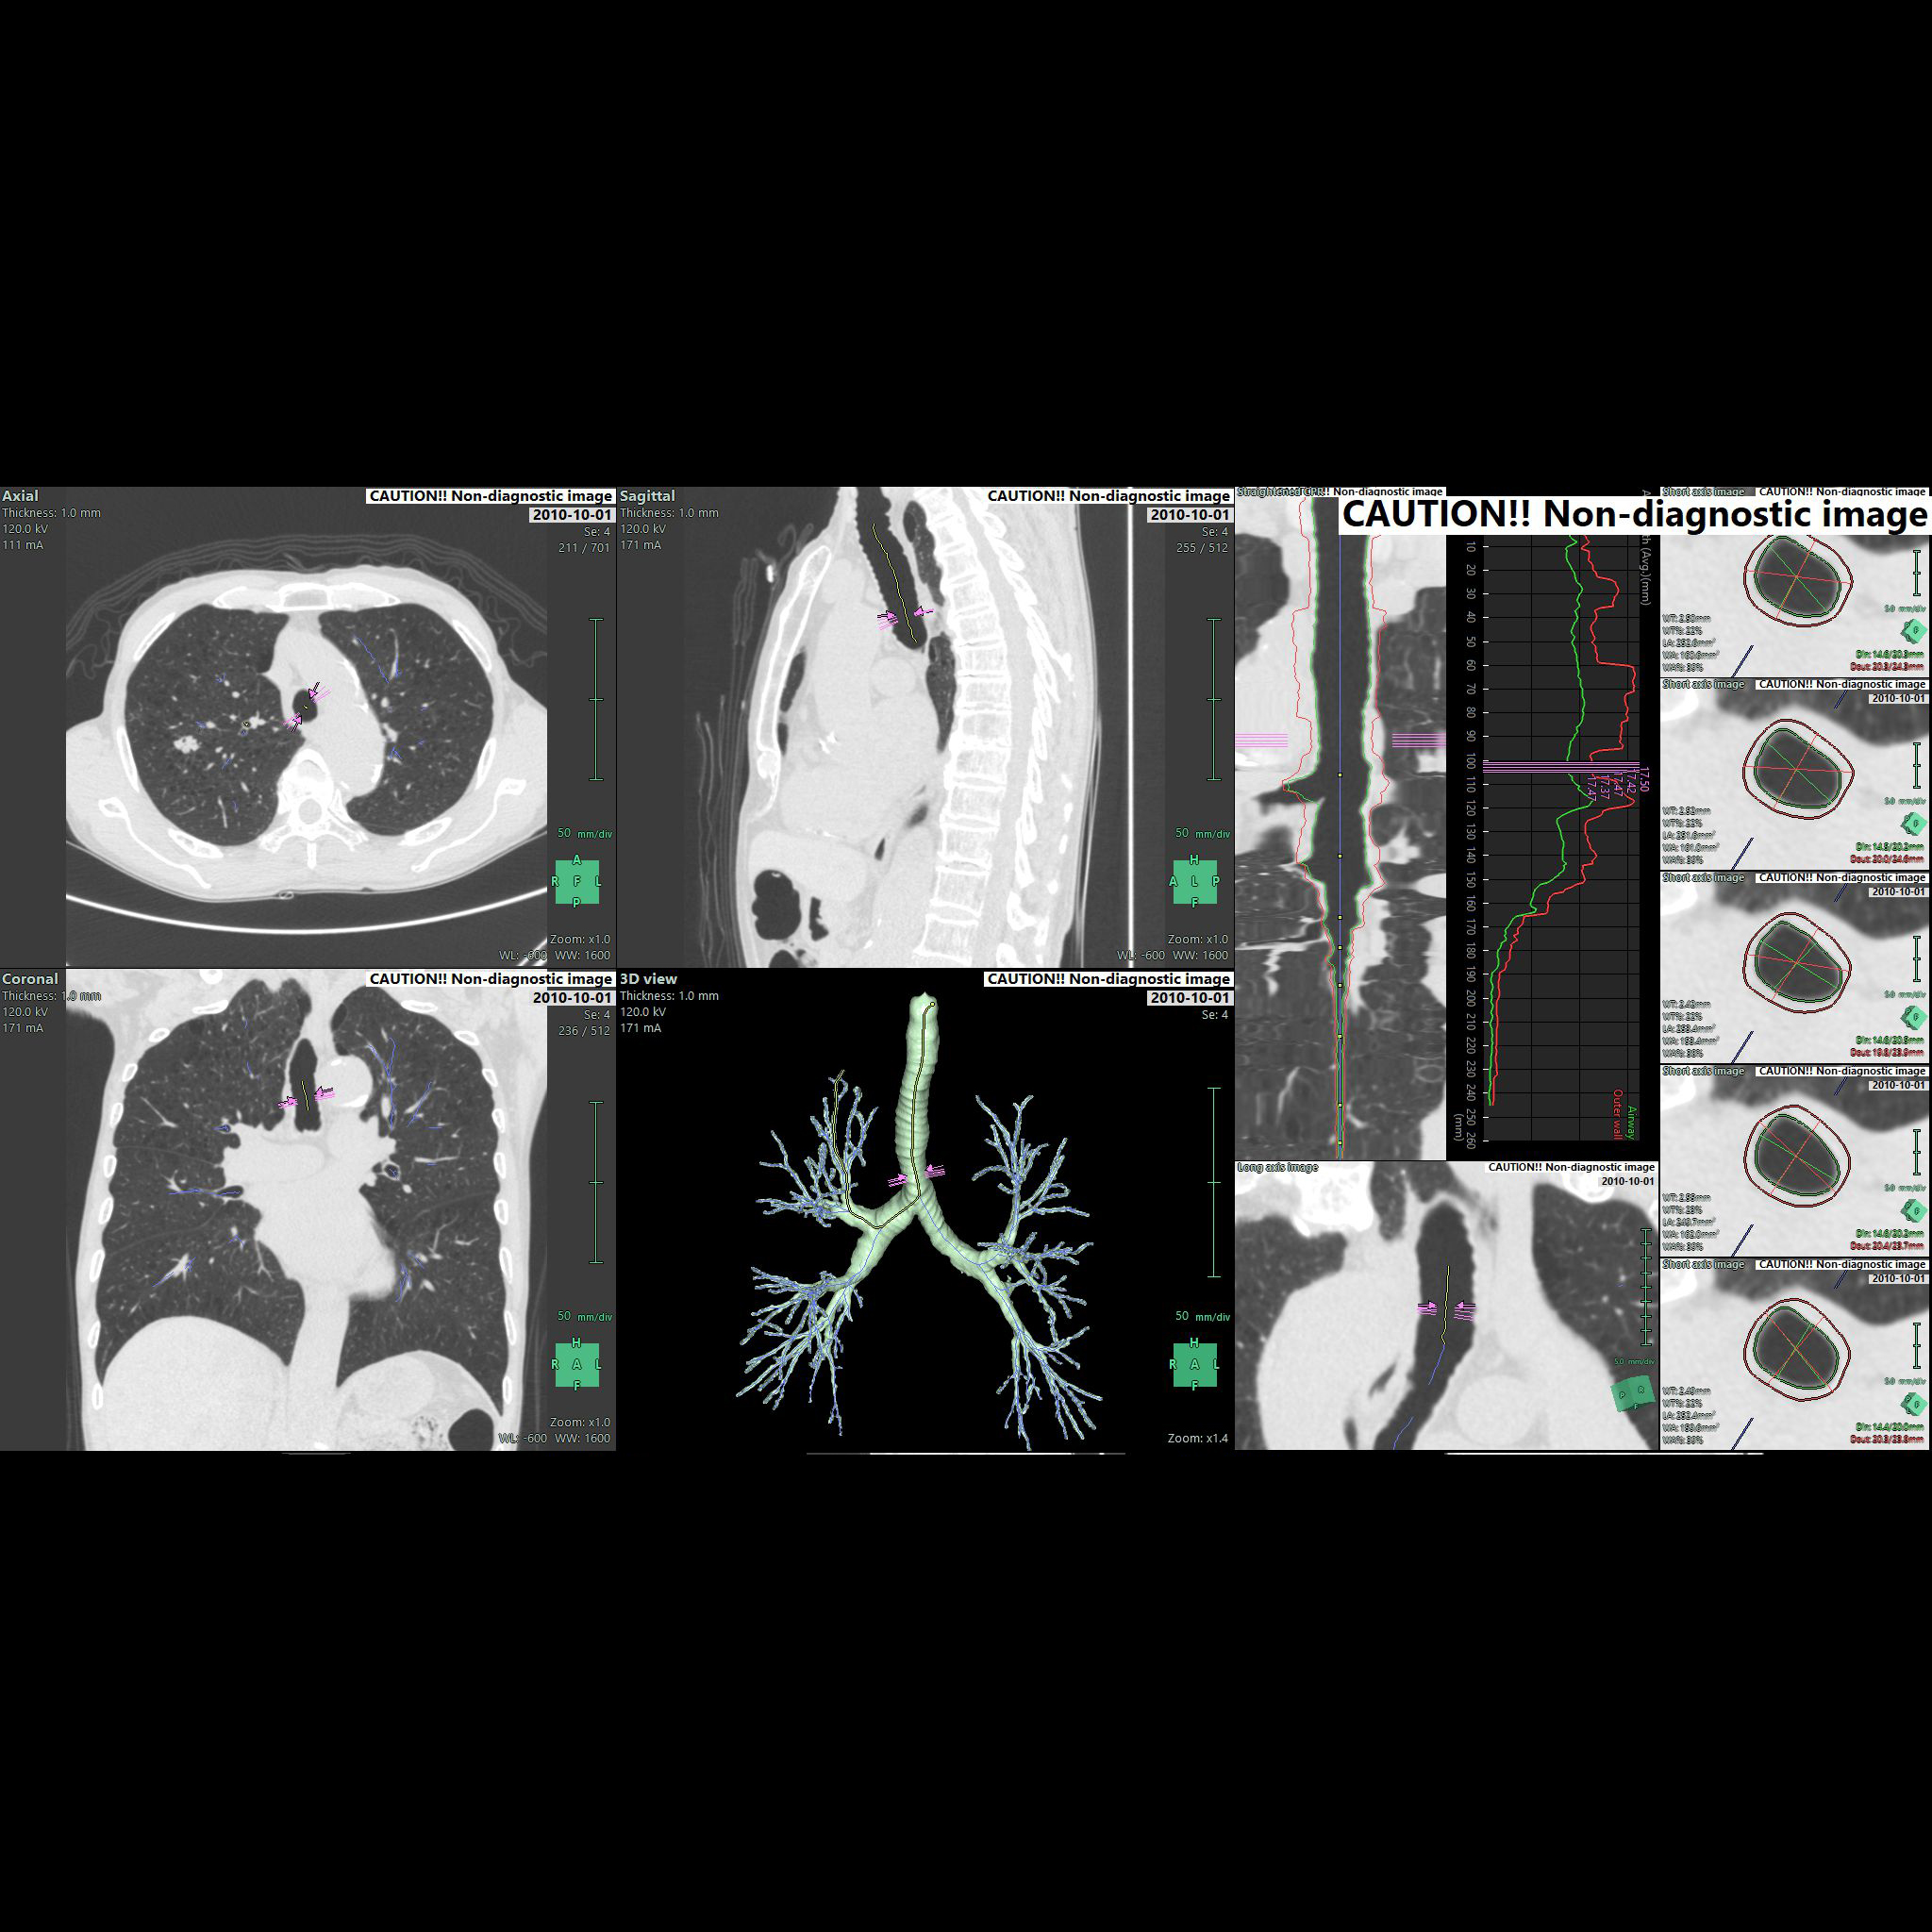

• - CT image를 사용하여 nodule까지의 path를 구성하고 관찰할 수 있습니다.

• - Bronchus의 직경 End-point부터 Nodule 까지의 거리 등을 확인하며 가상 내시경을 진행할 수 있습니다.

Bronchus CPR